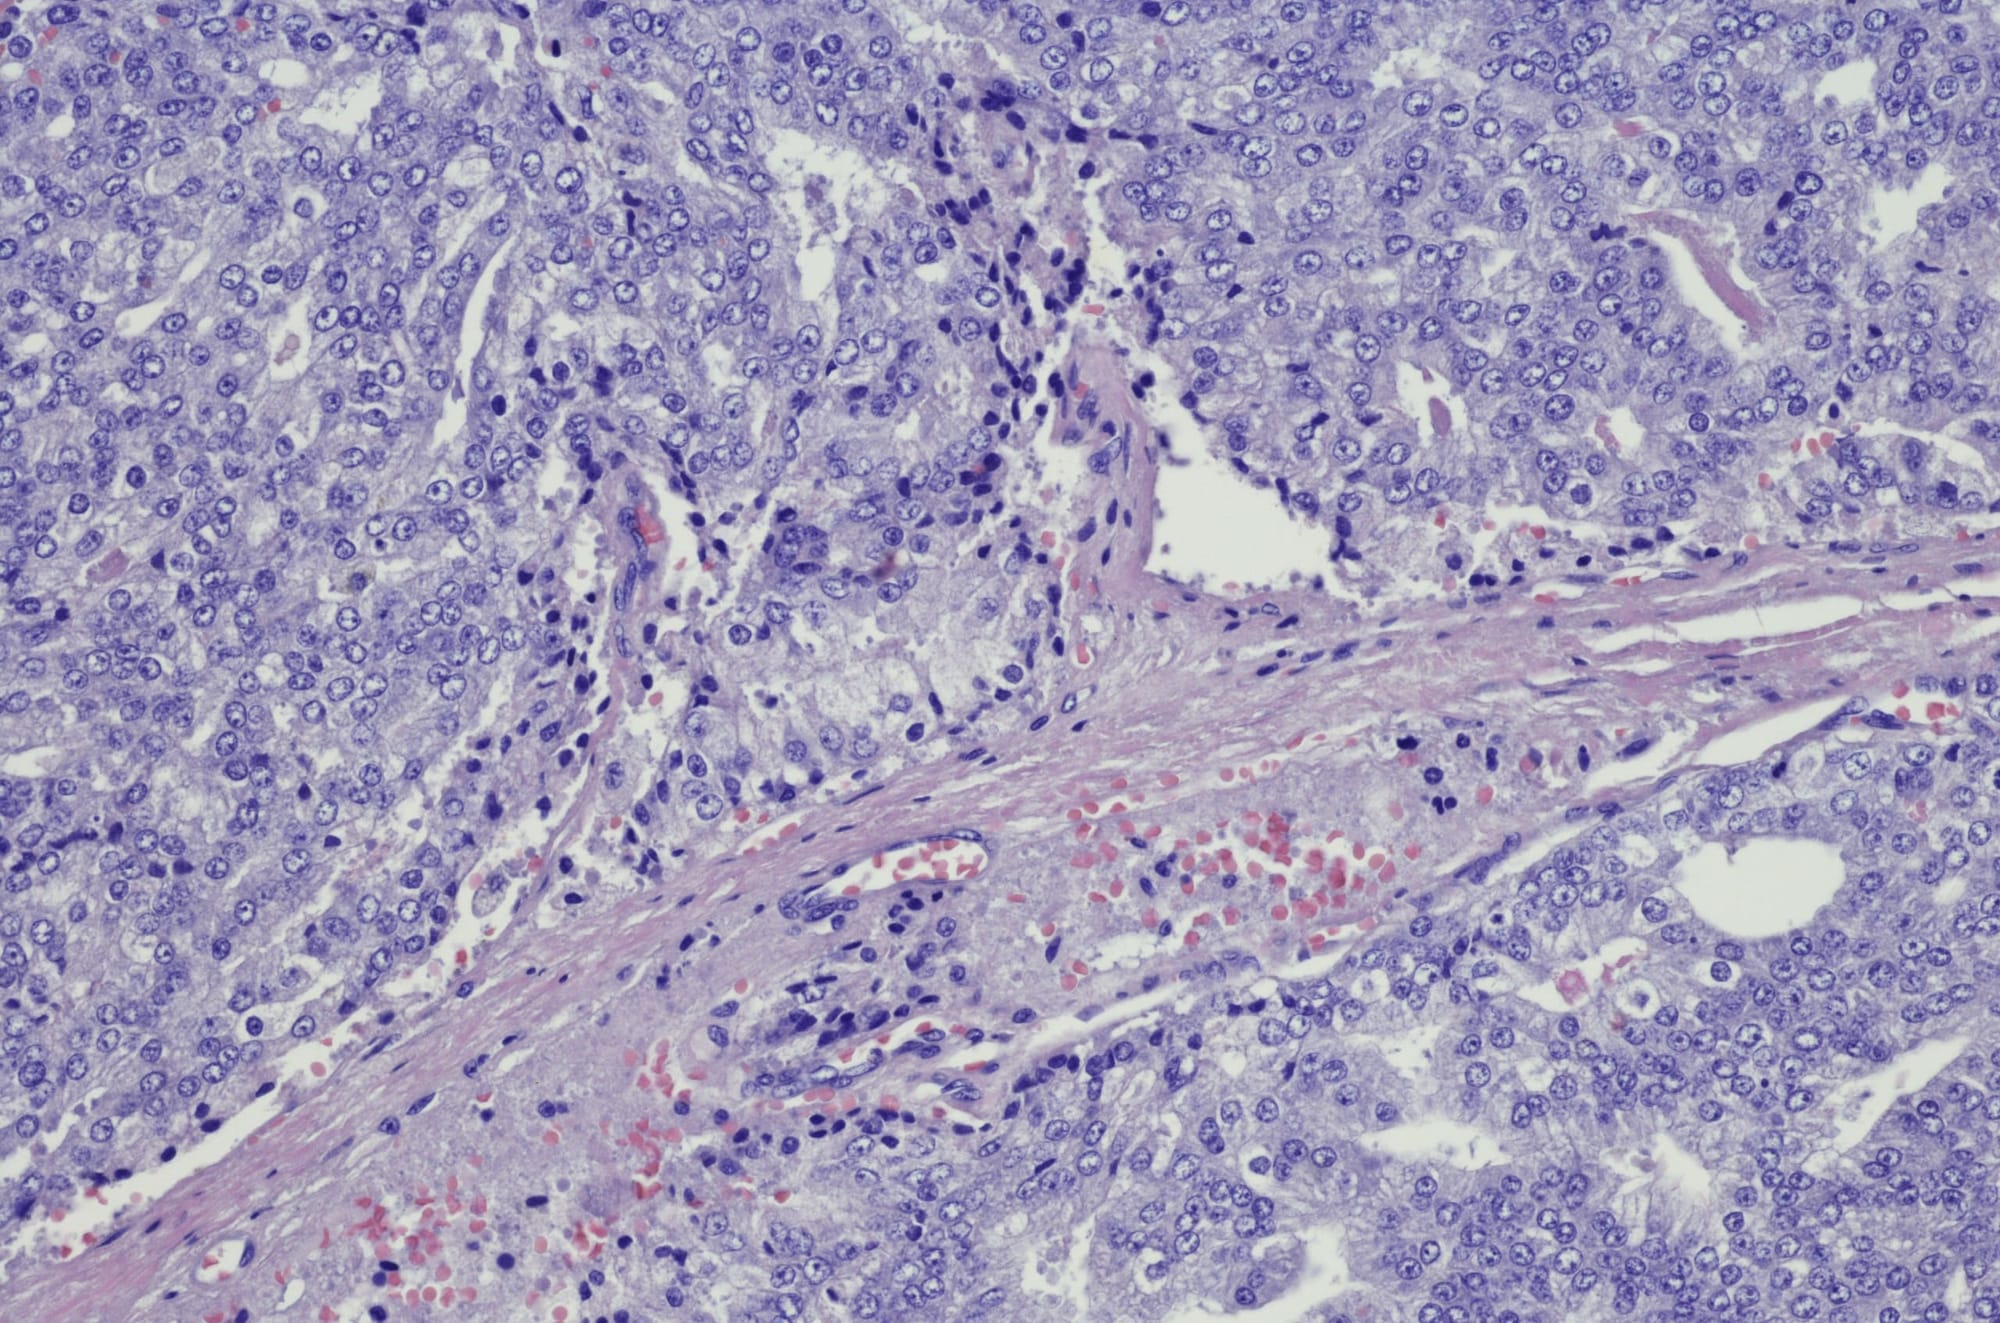

I’m invited to look at these live prostate cancer cells under the microscope, and suddenly they look less benign, more sinister. I squint to focus, and soon a foreboding, alien landscape reveals itself.

Healthy prostate cells look a little like the inside of a pomegranate, ordered, fairly uniform in shape and size and spacing.

Prostate cancer cells appear more haphazard, misshapen, clumped together randomly as they mutate and multiply without restraint.

The degree of chaos in the cells’ appearance reflects the aggressiveness of the cancer, and is measured by something called a Gleason Score. Mine registered an alarming nine out of 10 on diagnosis, which makes my continued good health even more surprising to my oncologist.